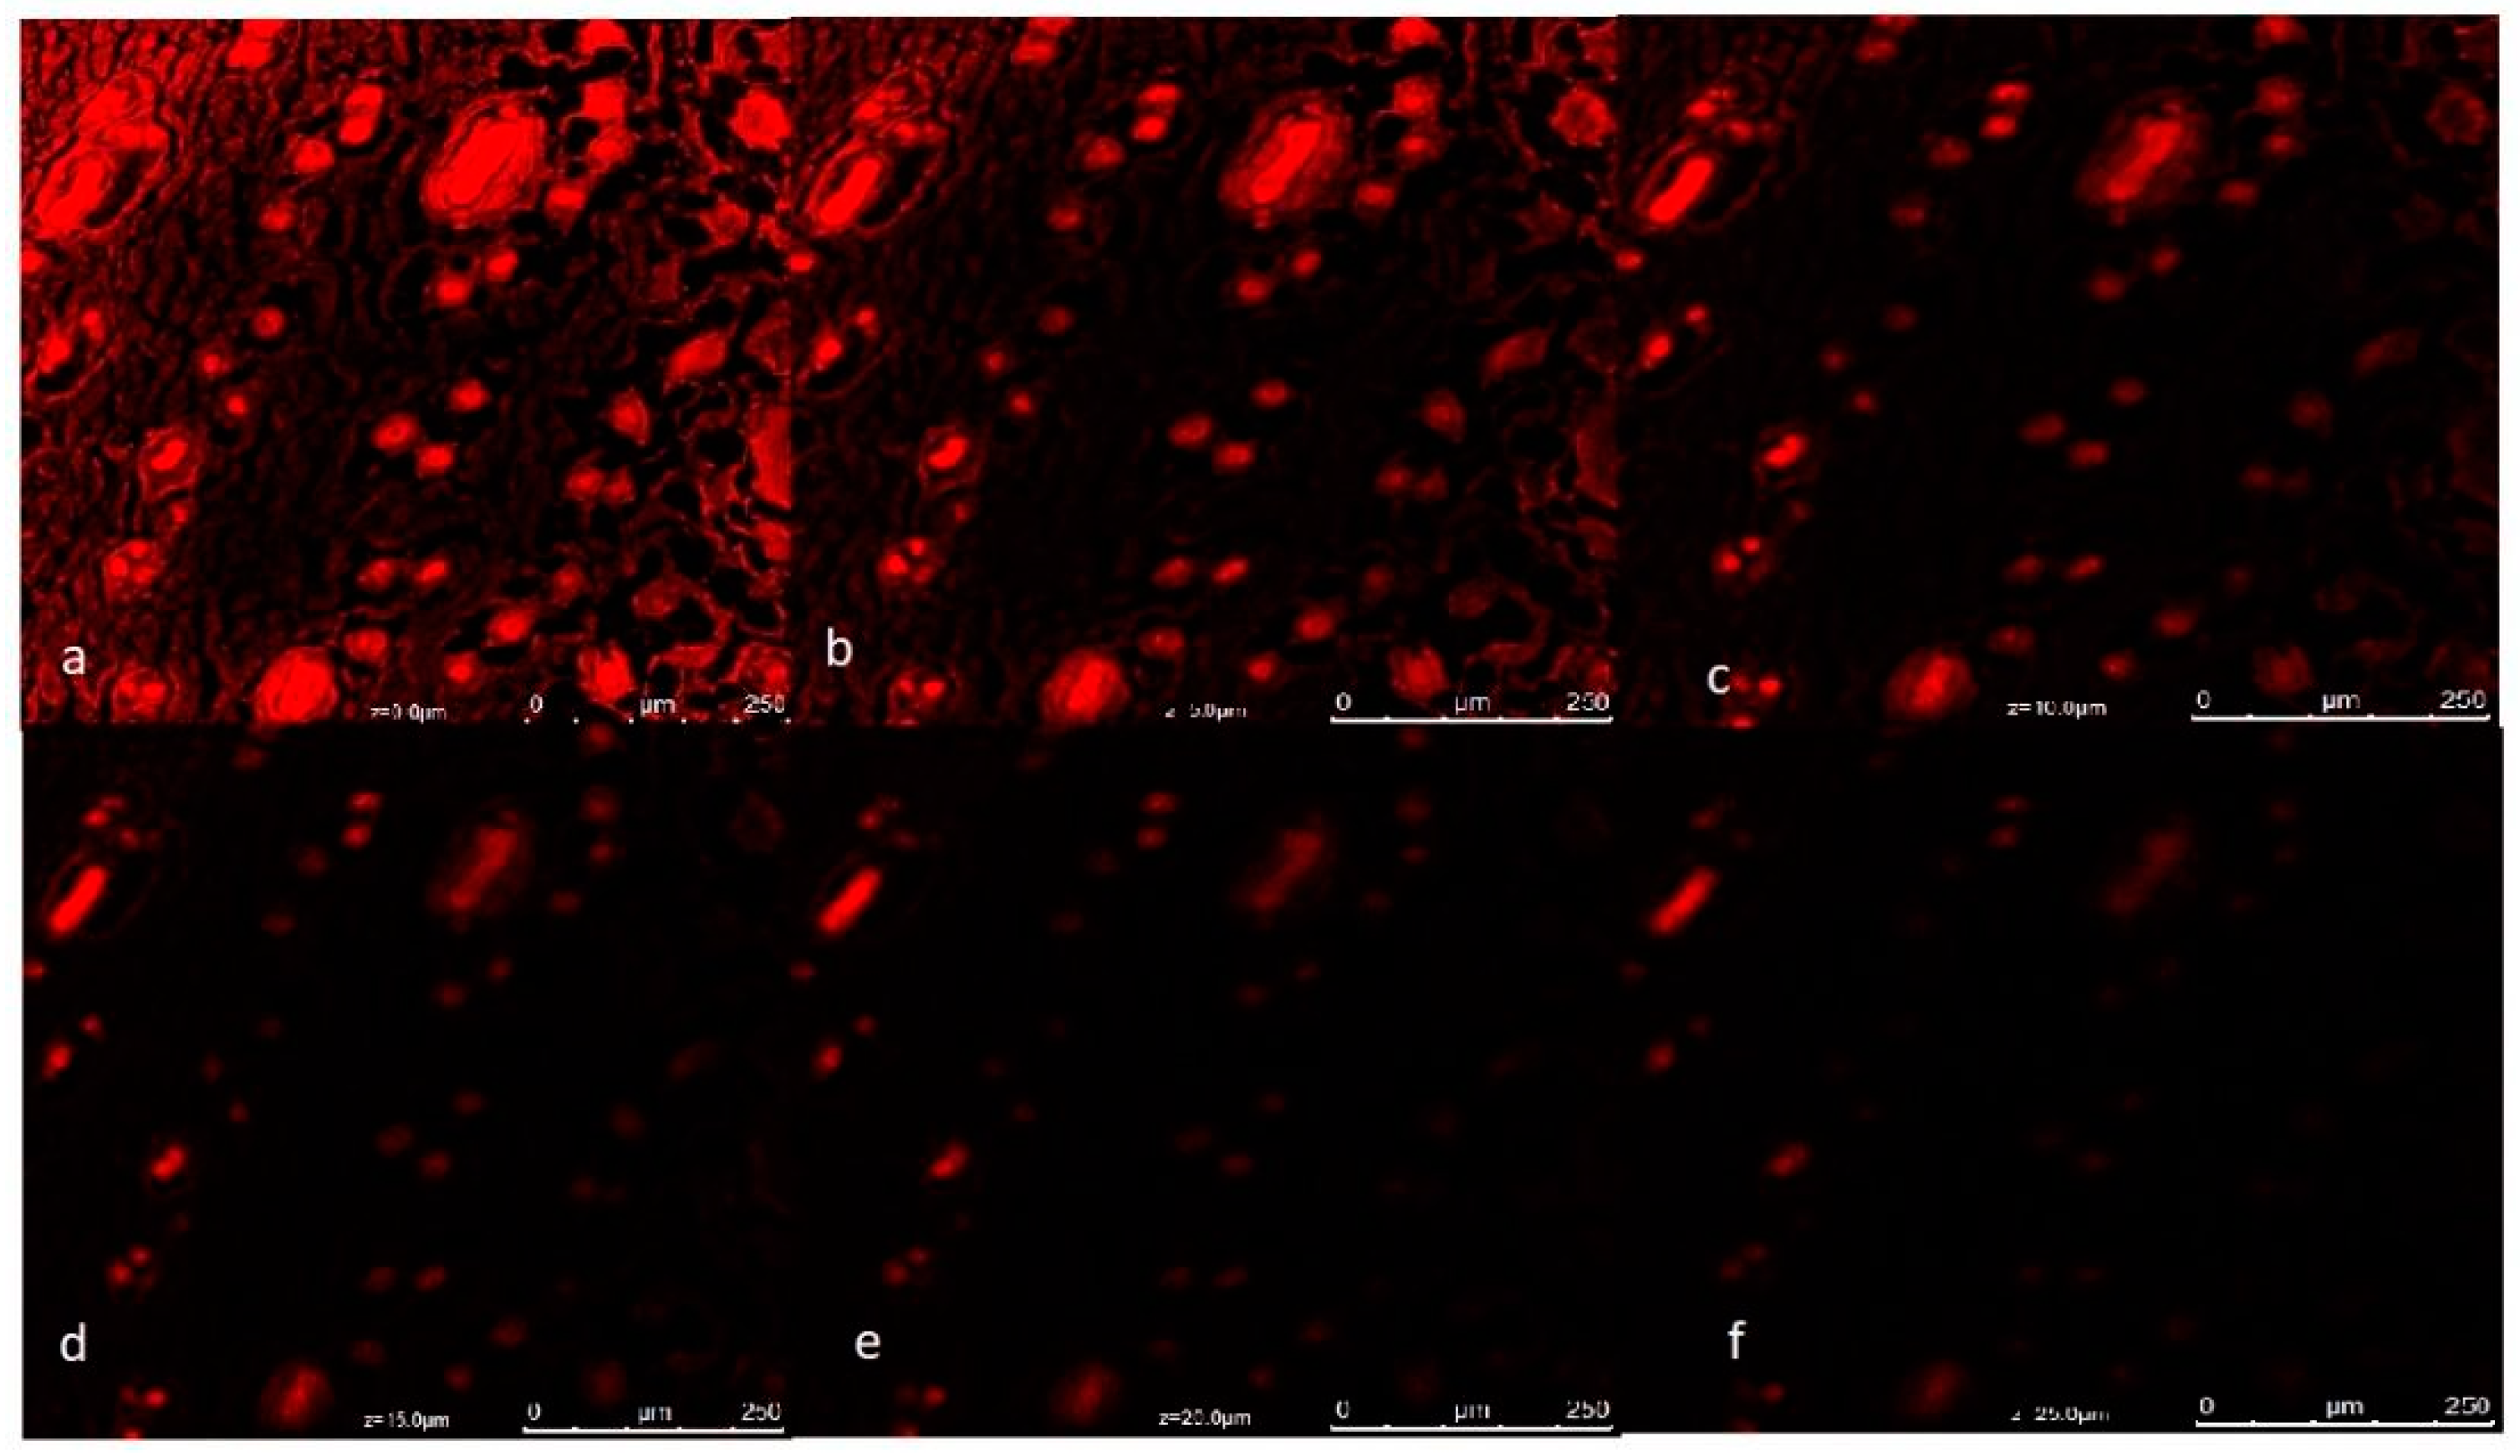

3.10. Confocal Laser Scanning Microscopy